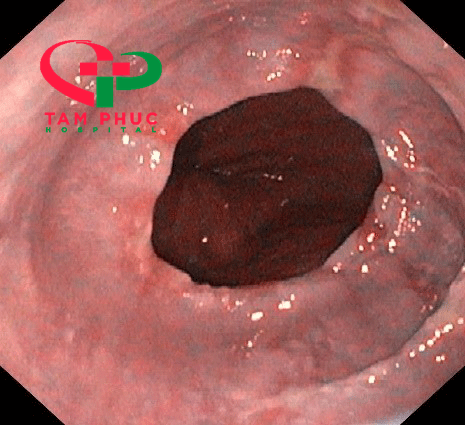

Bệnh viện tiếp nhận một bệnh nhân nam 48 tuổi vào viện vì nôn ói sau khi ăn, uống. Bệnh nhân được bác sĩ chỉ định siêu âm bụng tổng quát và nội soi dạ dày - thực quản.

Kết quả nội soi cho thấy: thoát vị hoành type I ( Hill VI), kèm trào ngược dạ dày thực quản Grade B (LA).

Hình ảnh nội soi tại BVĐK Tâm phúc.